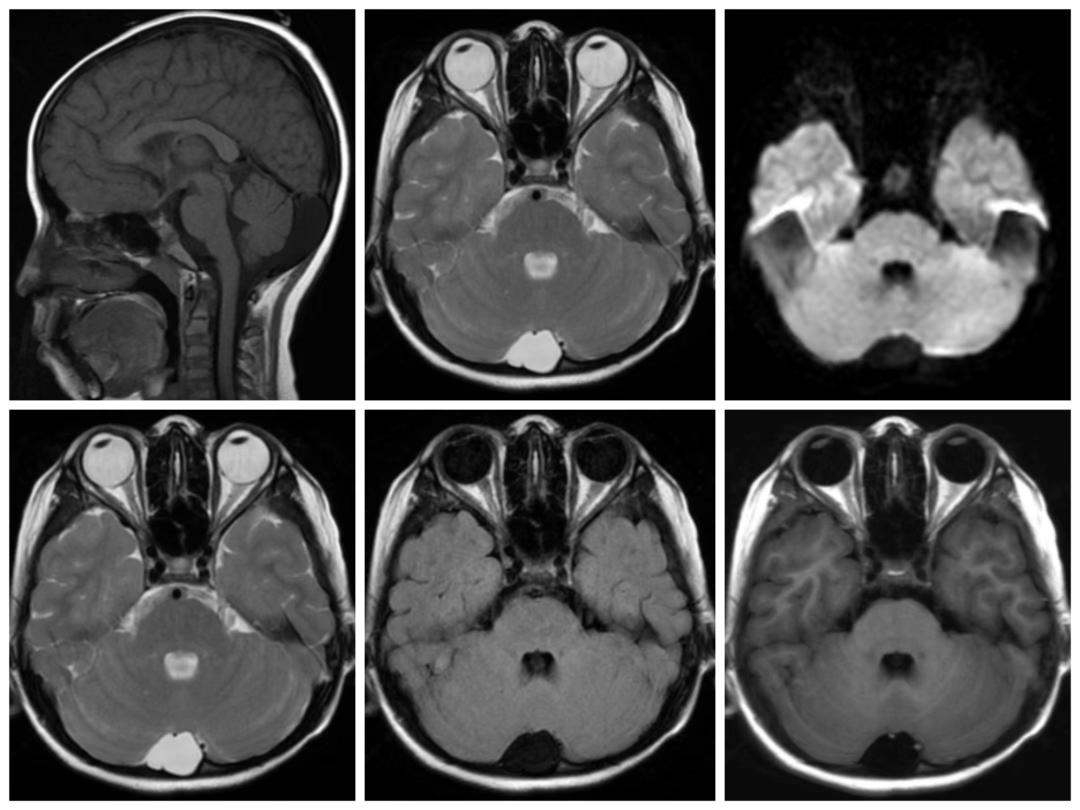

枕大池蛛网膜囊肿

蛛网膜囊肿or大枕大池?这些影像细节告诉你答案!

如何鉴别—大枕大池与枕大池蛛网膜囊肿